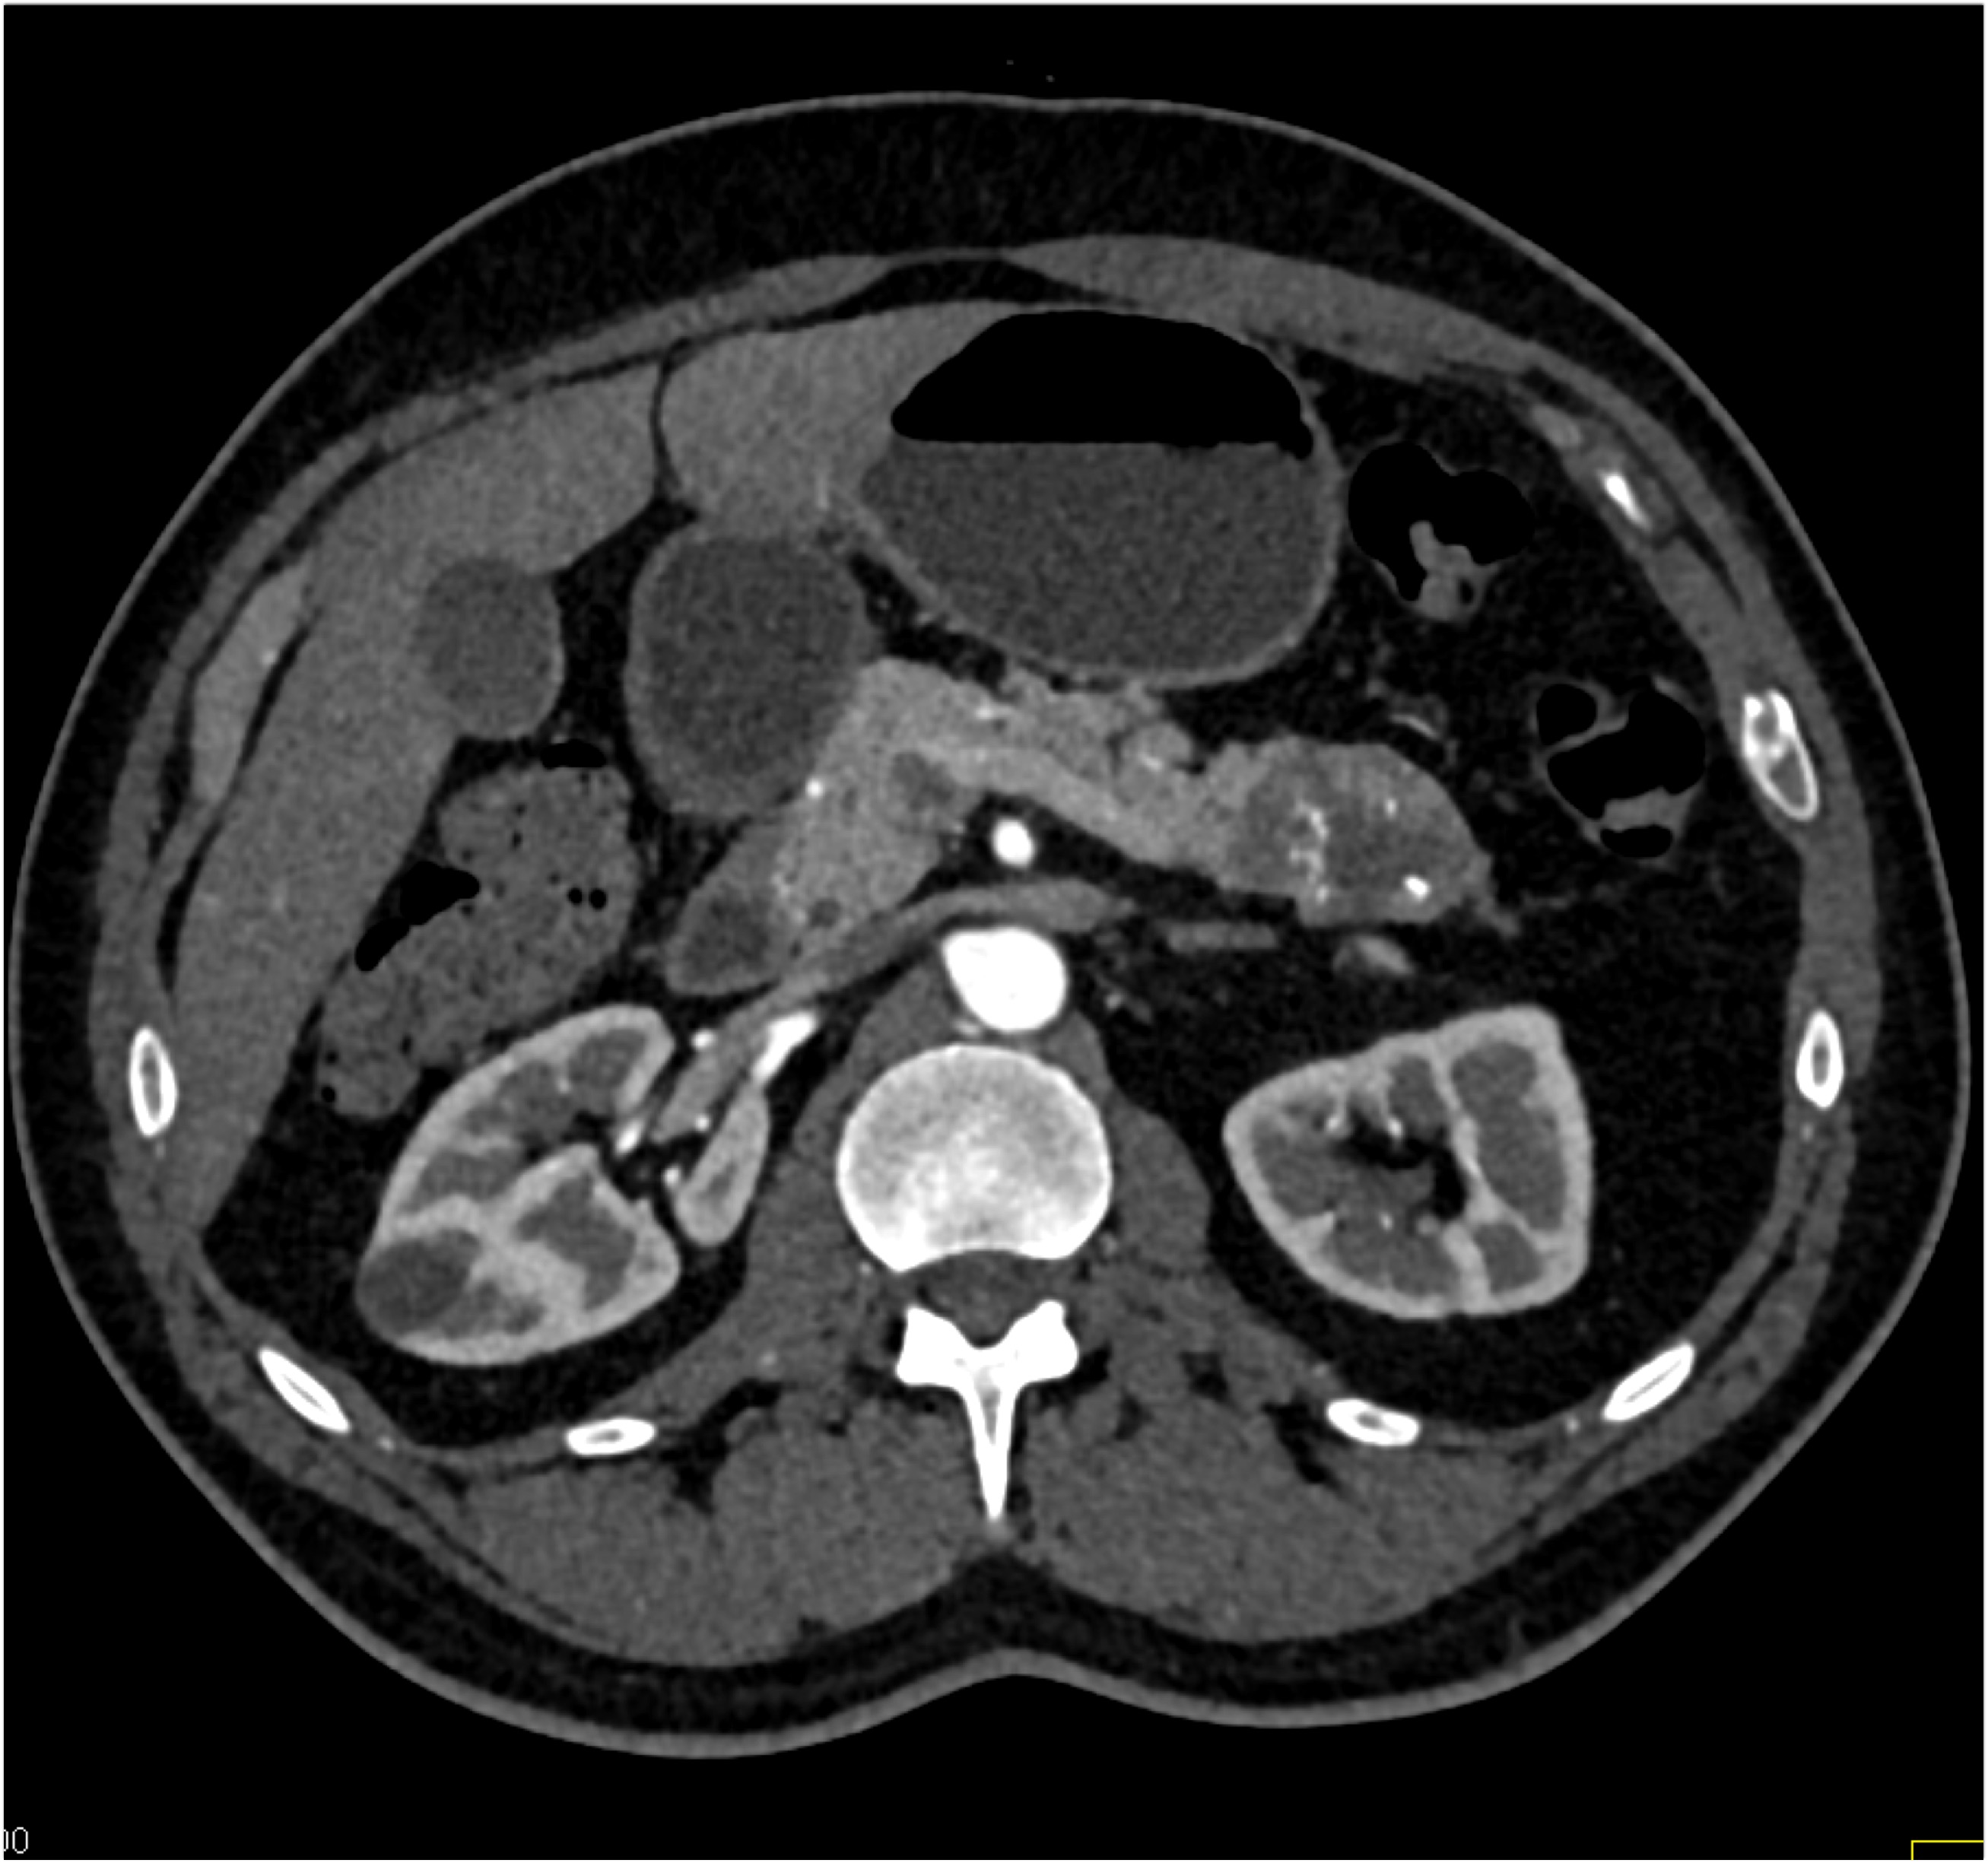

8) In this patient with RUQ pain and no history of trauma the best diagnosis is?

multiple hemangiomas

focal nodular hyperplasia

hepatic adenomas

angiosarcoma of the liver